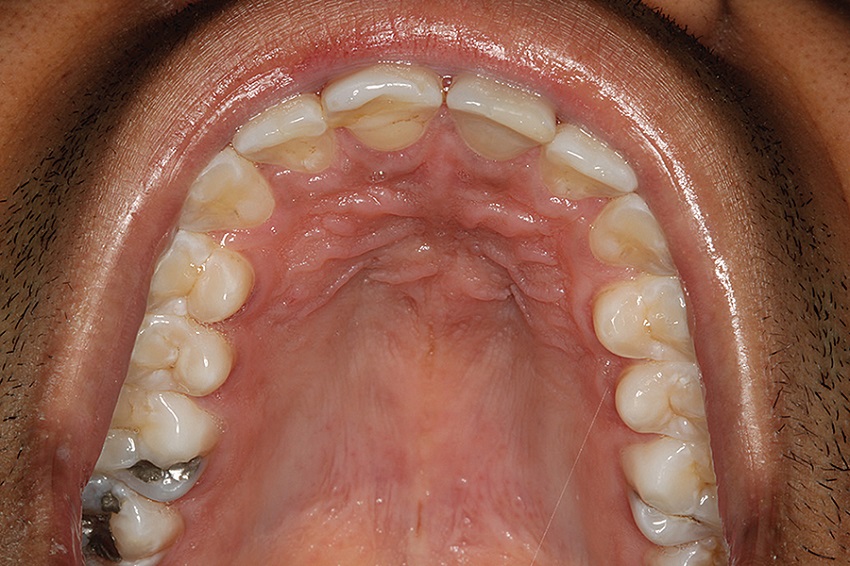

A 25-year-old male patient attended the Stomatology Clinic of the Department of Dentistry of the PUC Minas complaining of a painful swelling in the central region of the hard palate, with three weeks of evolution time. The patient did not present noteworthy systemic alterations. The extraoral examination showed no alterations. In the intraoral examination, we observed the presence of a nodule in the central region of the hard palate, with a soft texture, covered by preserved mucosa and normal coloring (Figure 10). The maxillary occlusal radiograph showed a unilocular radiolucent well-defined lesion, in the anterior region of the maxilla, measuring about 3 cm (Figure 11). Tests of pulp vitality of the teeth close to the lesion were performed to rule out the possibility of inflammatory lesions of endodontic origin. The results were positive, and the diagnostic hypothesis was nasopalatine duct cyst. Under local anesthesia, aspiration of the lesion fluid (positive for translucent fluid) and excisional biopsy were performed, following a surgical protocol similar to the previously reported case (Figures 12 and 13). The material was sent for anatomopathological examination (Figure 14). The histological sections, stained with HE, showed cystic cavity covered by non-keratinized stratified squamous epithelia and fibrous connective tissue capsule with neurovascular bundles, confirming the diagnosis of NPDC.